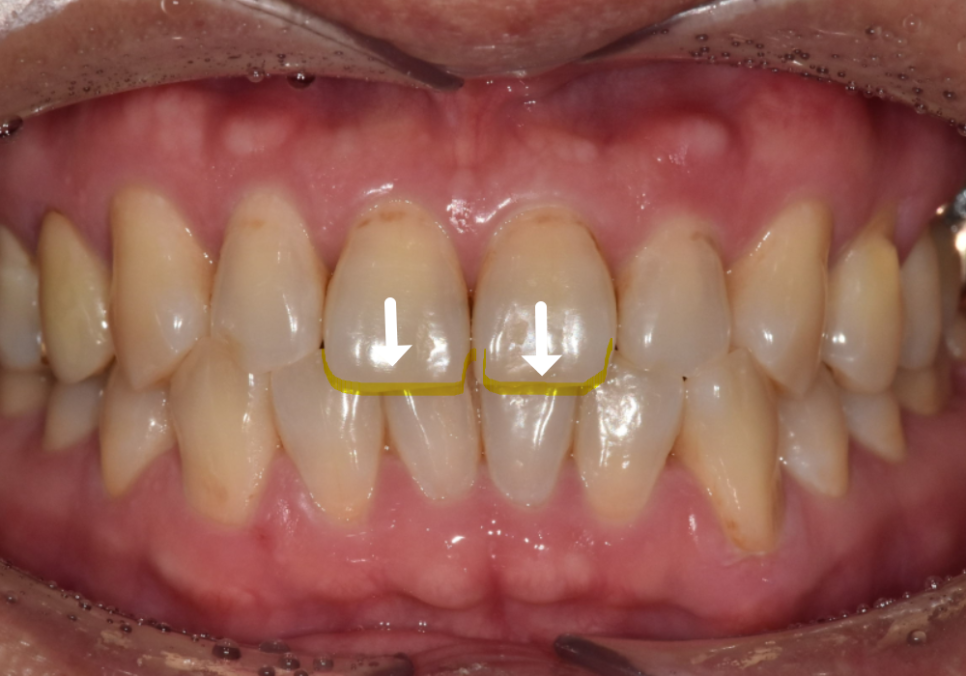

특히 절단교합은

위 앞니와 아래 앞니가 끝과 끝끼리

딱 부딪히는 구조라

레진이 정면에서 계속 충격을 받습니다.

그래서 “또 깨졌어요”라는 고민이 반복되는 것이죠.

하지만 절단교합은 다릅니다.

절단교합

위 앞니와 아래 앞니가 겹치지 않고

끝끼리 부딪힙니다.

힘이 모서리에만 꽂히니

금이 가기 쉬운 구조죠.

이 상태에서 레진으로 수복하면

음식을 씹을 때마다 충격이

레진 끝부분에 그대로 전달됩니다.

그래서 조금씩 깨지고, 떨어지고,

색도 변하게 되는 거죠.

오늘 소개할 환자분도

어릴 때부터 절단교합을 갖고 계셨습니다.

한 번 앞니가 깨진 뒤 레진으로 여러 번 수복했지만

씹을 때마다 같은 자리에 힘이 실리면서

또 깨지고, 또 변색되는 상황이 반복됐습니다.

최근에는 레진이 다시 깨지면서

오른쪽과 왼쪽 앞니 길이가 다르게 보이고

앞니가 살짝 앞으로 뻗어 보이는 돌출감도 겹쳐

웃을 때마다 더 신경 쓰인다며 내원하셨습니다.